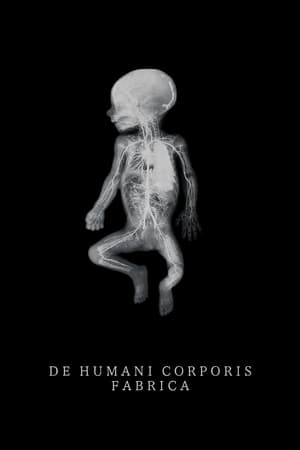

De humani corporis fabrica

(2023)Overview

An extraordinary adventure through the interior of the human body; or the discovery of an alien landscape of unprecedented beauty.